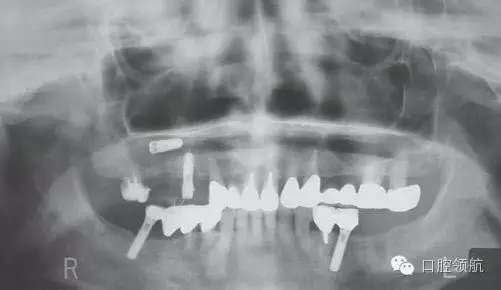

在外院進(jìn)行上頜竇提升術(shù)7~8個(gè)月后,二次手術(shù)時(shí)發(fā)現(xiàn)種植體松動(dòng),在去除種植體時(shí)發(fā)生種植體進(jìn)入上頜竇的情況。被介紹來我院就診,于當(dāng)日進(jìn)行了進(jìn)入竇種植體的去除術(shù)(圖1、圖2)。

圖1 來院時(shí)的曲面斷層影像。